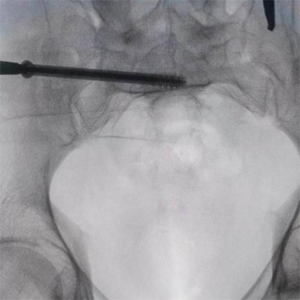

患者37岁,为高坠伤患者,入院合并颅脑挫伤、盆腔脏器出血、骨盆骨折多发伤患者。为最大限度降低手术风险,同时给予患者满意的手术疗效,术前综合评估患者病情,拟定行“天玑机器人”辅助定位下骨盆骨折微创手术。2月13日10时,手术正式开始。拉萨市人民医院采集患者术中二维影像,通过骨科手术机器人拟定螺钉打入位置方向后,吴宏华主任完成手术设计,成功为该患者置入了一颗高难度骶髂螺钉,出血5ml,切口1cm。术后图像显示,螺钉位置及方向完全符合手术规划,没有一丝偏差,手术成功。

透视下见置入的骶髂螺钉,位置、长度精准,无丝毫偏差